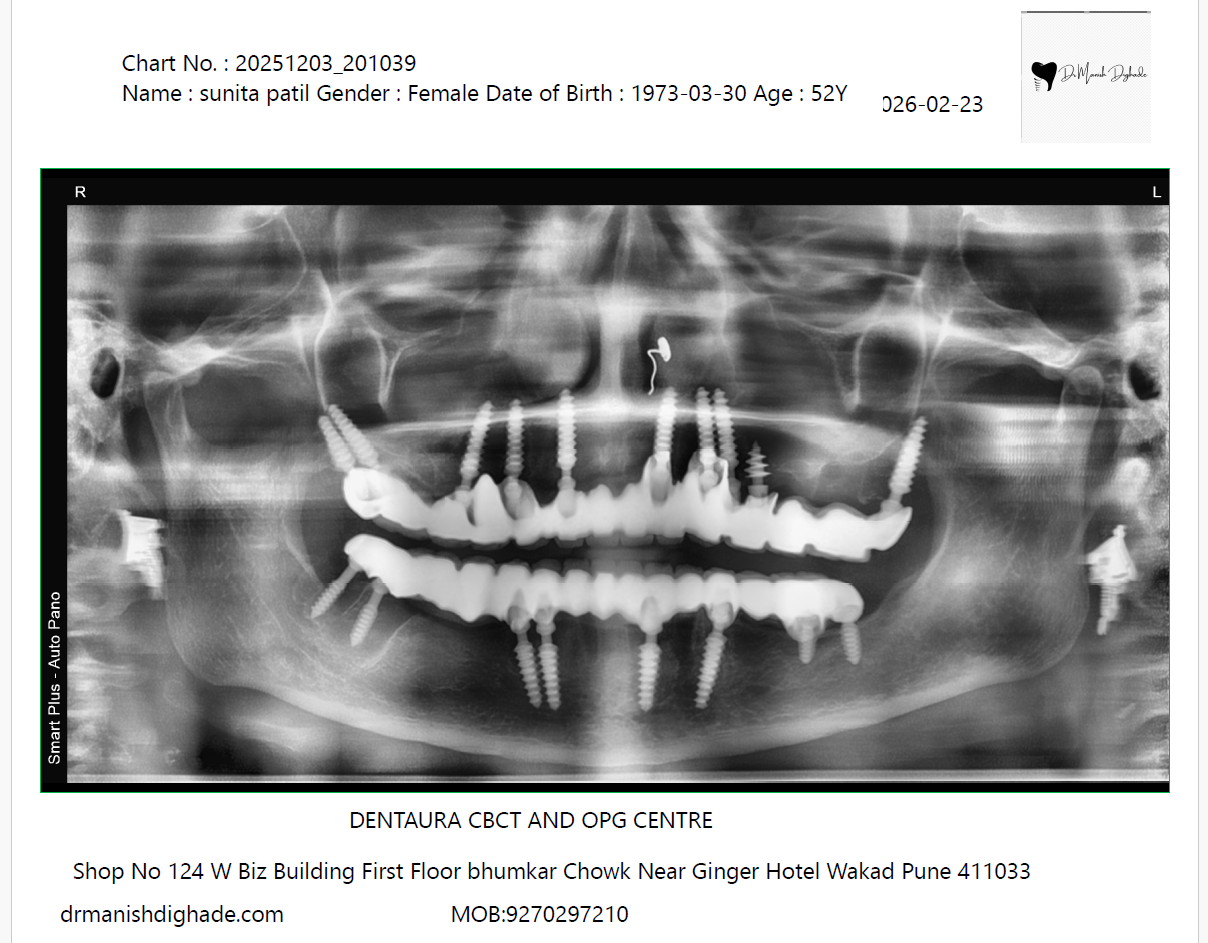

X-Ray Analysis

OPG — After

Radiographic Findings

The X-ray shows multiple dental implants placed in both the upper and lower jaws in a patient who previously had no natural teeth. These implants are strategically positioned in available bone areas to provide strong support for fixed teeth. Despite complete tooth loss, the implants allow full-mouth rehabilitation, restoring chewing ability and stability much better than removable dentures.